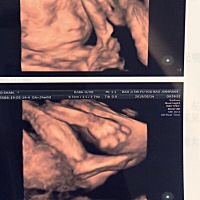

今天22周了哈🐷佩奇呵呵😄